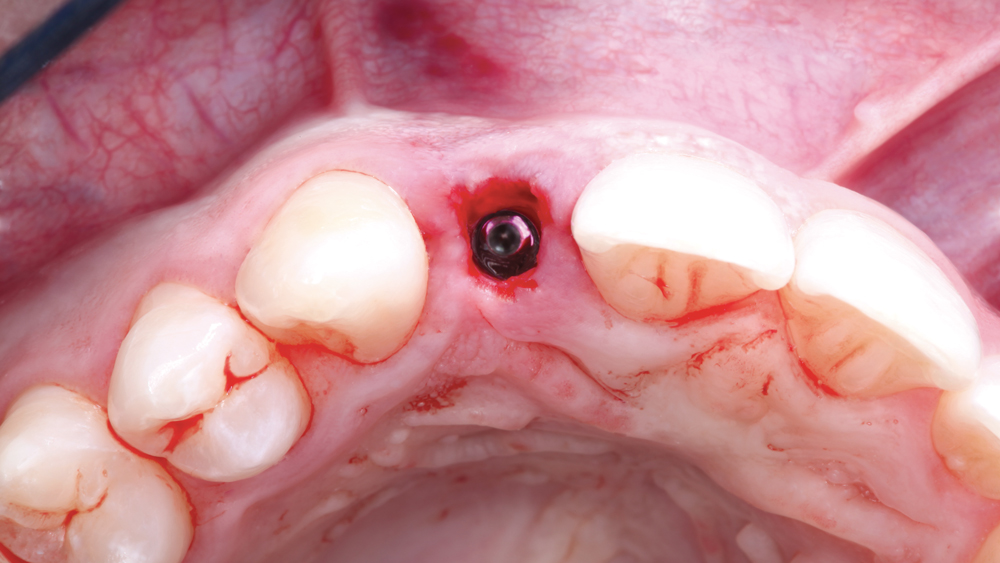

The following case illustrates the efficient, straightforward clinical workflow for placing Hahn Tapered Implants via guided surgery. A digital treatment plan is developed in which a 3.5 mm implant is positioned to support the ideal prosthetic outcome. An immediate provisional crown is designed in concert with the surgical guide and delivered at the time of surgery, helping to produce a predictable, highly esthetic restoration for a demanding case in the smile zone.